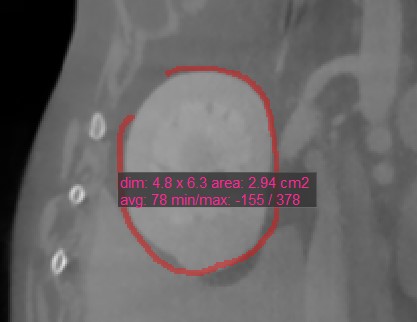

Some of the CT Viewer measurement tools are used to mark an area on the active image slice. There are four values which are automatically calculated and displayed alongside these measurements.

Dim: Dimensions of the measurement (width, height, distance)

Area: The area inscribed with the measurement, calculated in square centimeters

Average: The average tissue density value (HU) inscribed by the measurement. Higher HU values indicate denser tissue, such as bones.

Minimum/Maximum: The minimum and maximum value indicate the minimum and maximum tissue density value inscribed by the measurement.

Oval¶

Select the Oval tool and assign it to one of the available mouse buttons. Start the measurement by pressing on the active image slice and drag the mouse to obtain an oval shape. Release the mouse when satisfied

with the size of the marked area.

All available measurement values are displayed alongside the measurement.

Modify the marked area by moving one of the four points describing the rectangle around the oval shape using the Default tool.